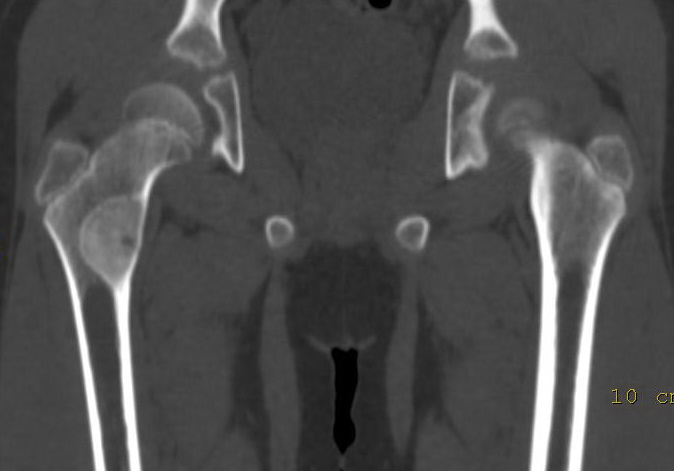

以下是引用lkc8963在2009-2-23 9:48:00的发言:[br]骨纤维性病变--非骨化性纤维瘤或局灶性骨纤首先考虑.理由:磨玻璃改变,边界清,向髓腔侧及皮质侧膨胀.最需鉴别内生软骨瘤,请楼主在轴扫上看有无点环状钙化,本例第二张图片上似见钙化,如有钙化首先考虑软骨源肿瘤.

以下是引用zbp537在2009-2-23 9:49:00的发言:[br]典型的磨玻璃样改变,考虑骨纤或骨化性纤维瘤。